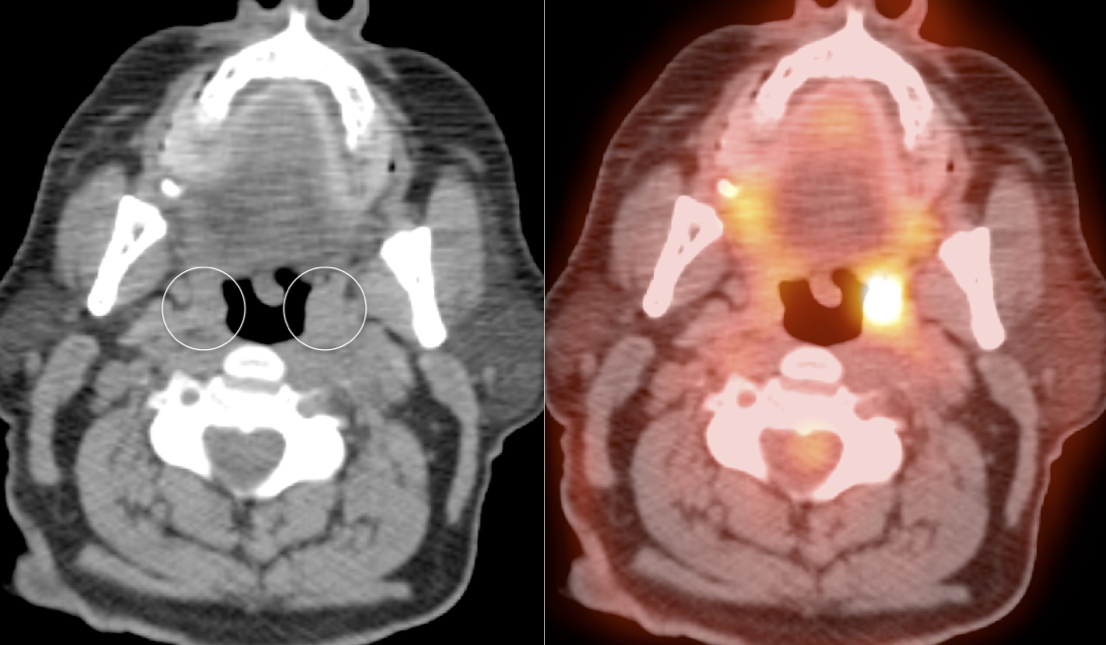

The palatine tonsils frequently demonstrate significant metabolic activity.

Bilateral and fairly symmetric FDG-uptake in non-enlarged palatine tonsils is typically a normal finding, and is usually not mentioned in a report.

Bilateral and fairly symmetric FDG-uptake in enlarged palatine tonsils is nearly always inflammatory in nature (although can be seen with lymphoma).

Unilateral FDG-Avid Tonsil (or Relative Increased Avidity of One Tonsil):

Special care is required when assessing the incidental finding of a unilateral hot tonsil (or relative increased uptake within one tonsil) — even though most unilateral hot tonsils are benign. Proposed techniques for assessment have included SUV threshold cutoff values, metabolic tumor volume assessment, and SUV ratios.